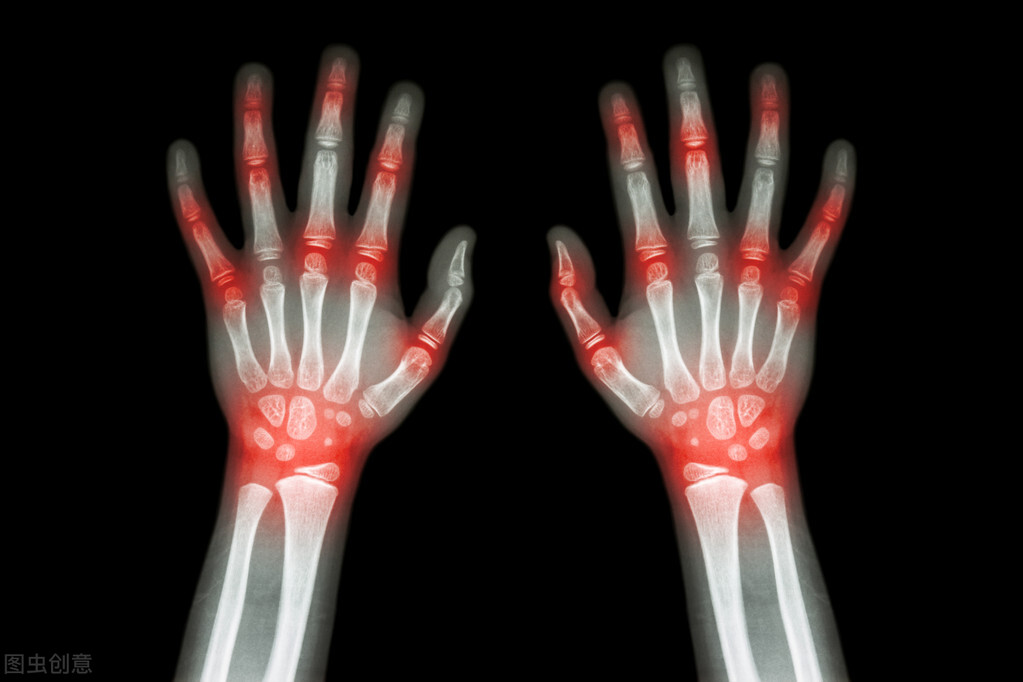

风湿病可侵犯全身多处关节及其他组织

类风湿关节炎以高畸形和高致残而闻名

类风湿关节炎关节病变严重程度分级